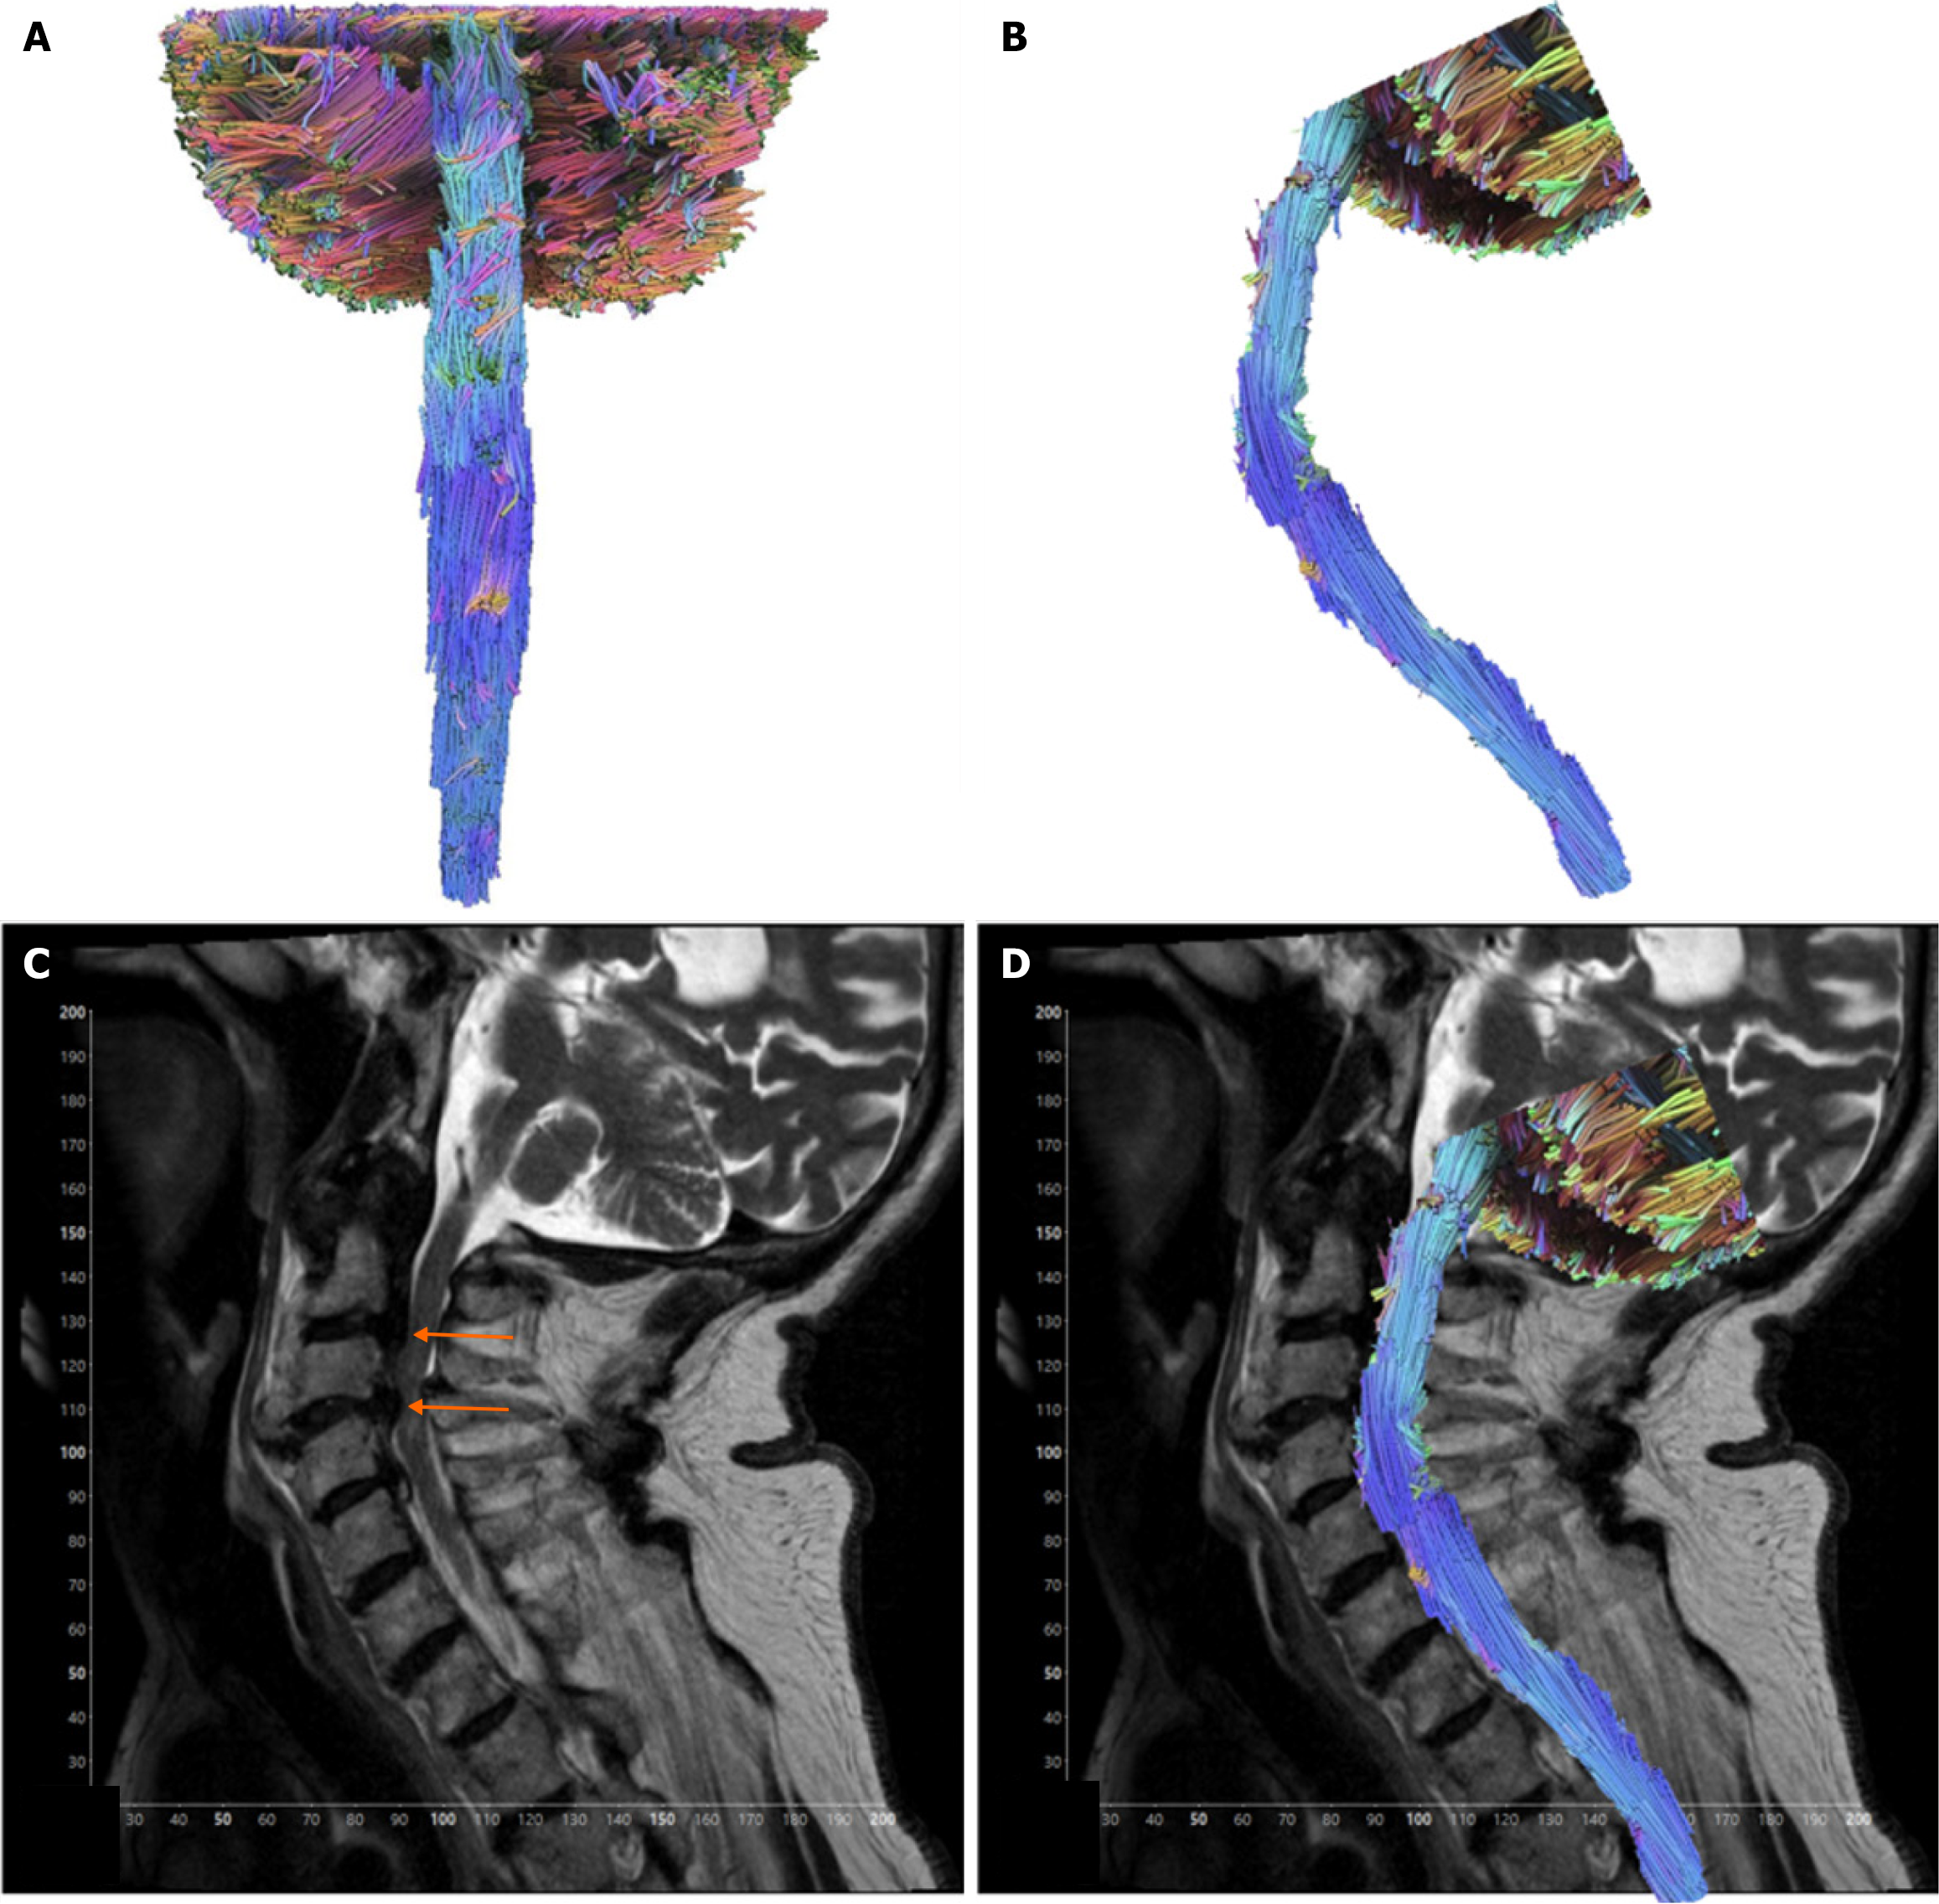

Figure 2 Contusion case.

A: AP view of tractography model. Case of an 82-year-old male presenting with spinal cord contusion; B: Sagittal view of the tractography model; C: T2-weighted sagittal view of the cervical spinal cord showing severe spinal canal stenosis from disc herniation and degenerative spondylosis at the levels of C2-C3 and C3-C4, with severe spinal cord flattening at C3-C4 (orange arrows); D: Sagittal view tractography model of contusion case superimposed over T2-weighted imaging of the cervical spinal cord.